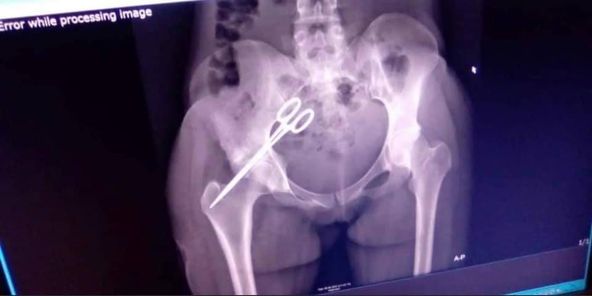

Scissors has been removed from the pelvic area of Sierra Leonean lady, Zainab Kamara, 7 years after Doctor’s negligence left her in that state.

Kamara who went for a Caesarian operation and lost the baby at Port Loko district was left with constant pains after a doctor that operated her forgot scissors inside her Stomach that later moved to her pelvic.

Sierraloaded learnt that She has been suffering with this pain for 7years and later an X-ray was done on her and the results shows Scissors is in a pelvic area according to sources doctors were scared to do the operation because they think it’s a risky one.

After 7 years the Scissors was removed by an Expert from another country at the Masanga Hospital in Tonkolili District.